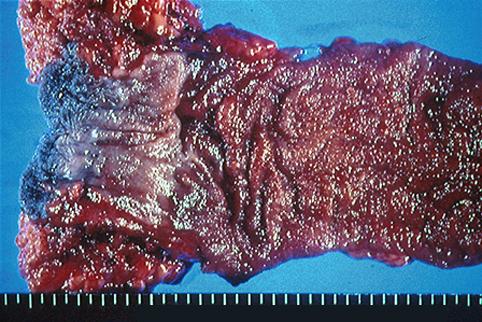

疾患(病理主体)の分類悪性上皮性腫瘍/腺癌

部位(臓器別)大腸/2区域以上の大腸にまたがるもの

検査方法マクロ

腫瘍の肉眼分類4型(びまん浸潤型)/

病変の最大径(ミリ)40以上

腫瘍の深達度ss(a1)